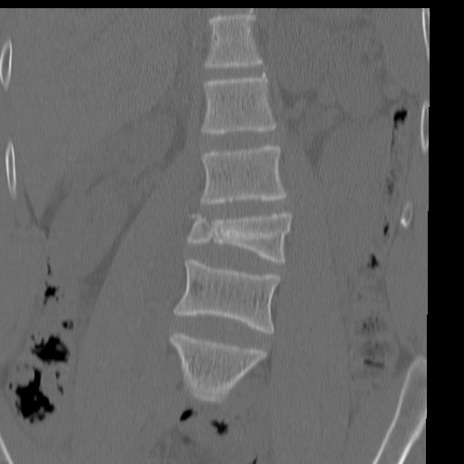

症例3 腰椎CT(冠状断像)

腰椎CT